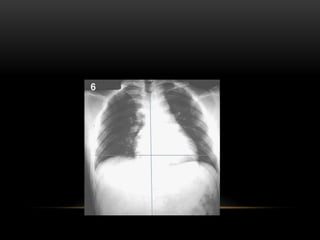

Que la radiografía este bien centrada.

El aumento de exposición de la radiografía.

Se debe tomar en inspiración profunda.

Sub- Exposición

SOBRE-EXPOSICIÓN

MISMA PLACA EN ESPIRACIÓN.

RX DE TORAXPA Que la radiografía este bien centrada. El aumento de exposición de la radiografía. Se debe tomar en inspiración profunda. Sub- Exposición

SOBRE-EXPOSICIÓN -Excesiva intensidad de radiación. -Enestas condiciones una lesión pulmonar que normalmente daría origen a una sombra tenue puede pasar inadvertida. -La estructura ósea de la columna se ve con toda claridad

MISMA PLACA ENESPIRACIÓN.